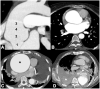

Non-traumatic thoracic aorta emergencies are associated with significant morbidity and mortality. Diseases of the intimomedial layers (aortic dissection and variants) have been grouped under the common term of acute aortic syndrome because they are life-threatening conditions clinically indistinguishable on presentation. Patients with aortic dissection may present with a wide variety of symptoms secondary to the pattern of dissection and end organ malperfusion. Other conditions may be seen in patients with acute symptoms, including ruptured and unstable thoracic aortic aneurysm, iatrogenic or infective pseudoaneurysms, aortic fistula, acute aortic thrombus/occlusive disease, and vasculitis. Imaging plays a pivotal role in the patient's management and care. In the emergency room, chest X-ray is the initial imaging test offering a screening evaluation for alternative common differential diagnoses and a preliminary assessment of the mediastinal dimensions. State-of-the-art multidetector computed tomography angiography (CTA) provides a widely available, rapid, replicable, noninvasive diagnostic imaging with sensitivity approaching 100%. It is an impressive tool in decision-making process with a deep impact on treatment including endovascular or open surgical or conservative treatment. Radiologists must be familiar with the spectrum of these entities to help triage patients appropriately and efficiently. Understanding the imaging findings and proper measurement techniques allow the radiologist to suggest the most appropriate next management step.